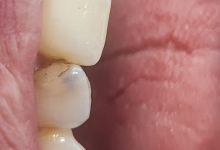

Clinica LUY ESTHETIC ART dispune de ultimele tehnologii in domeniul stomatologic si ofera solutia tratamentelor endodontice, pentru a incerca sa salveze un dinte care a fost distrus in proportii mari. Specialistii nostrii efectueaza acest tratament in mod corespunzator, pentru a evita aparitia altor complicatii ce implica interventii mai complexe: rezectia apicala sau riscul de a pierde dintele.

Stresul, fumatul, o igiena dentara precara, dar si modul de alimentatie duc la formarea cariilor. Acestea, netratate, favorizeaza aparitia infectiilor care vor dezvolta chisturi. Astfel de probleme se trateaza cu ajutorul tratamentului endodontic, zona respectiva fiind bine izolata pentru a preveni alte infectii. Atunci cand masurile nu sunt luate din timp, pulpa infectata moare si se formeaza chisturi la nivelul radacinii, iar interventia va deveni mai complexa.